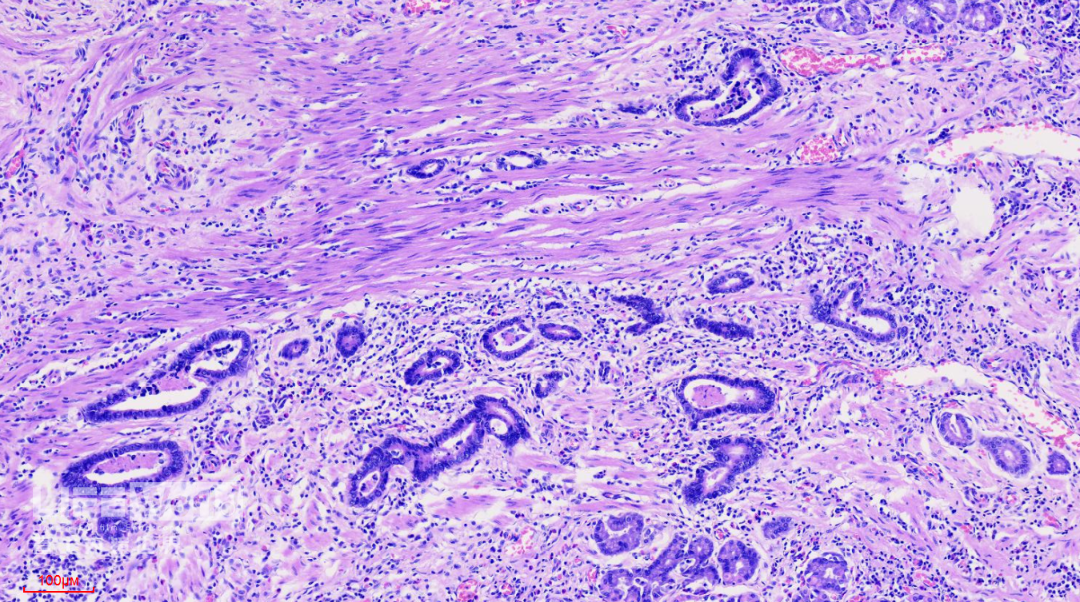

HE染色:2号切片示中分化腺癌,6号切片示高级别上皮内瘤变,局灶癌变。

这是2号切片,病变位于一条皱襞顶端。

病变处(红圈内)可见不规则的腺管状结构,部分呈筛网状。图中可以看出,病灶间可见相对正常的胃底腺结构。图片中最深的病灶已经侵及粘膜肌层。

此为病变最深的地方,癌变的腺管侵及粘膜肌层。

CK-pan染色显示肿瘤细胞为上皮细胞,呈不规则腺管状排列,提示为中分化腺癌。

SMA染色:粘膜肌层完整,肿瘤细胞侵及粘膜肌层,但未突破。